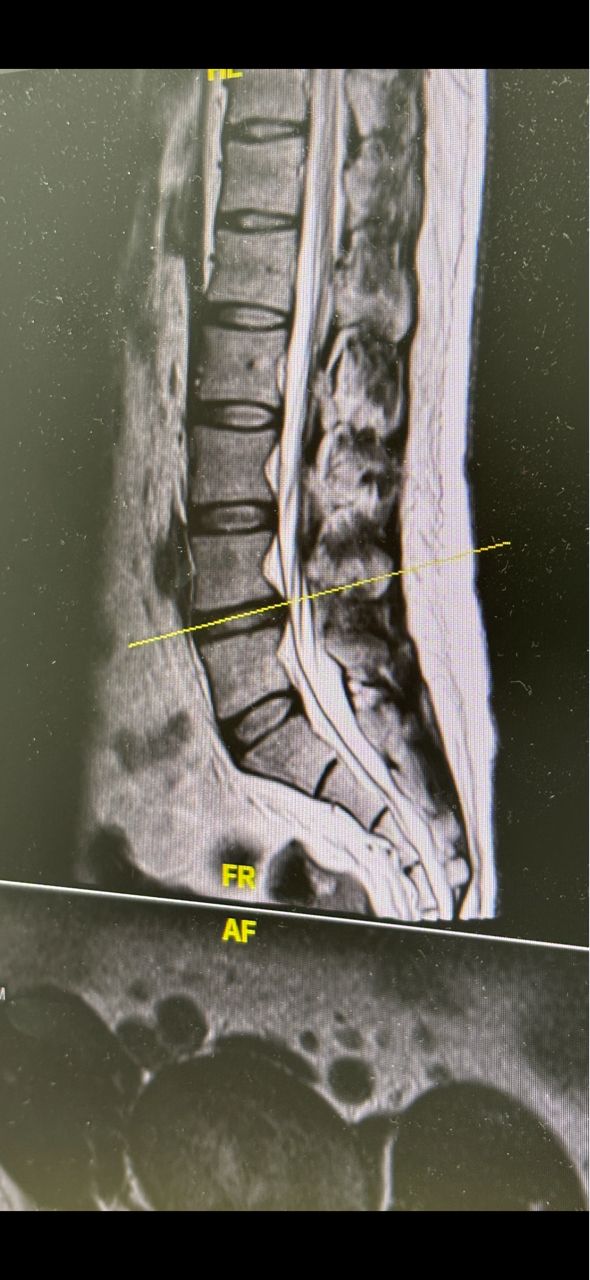

腰痛已經是10年的老毛病了 但近半年突然增加了大腿到小腿極爲酸痛的症狀 坐30分鐘就痛到不行 而且腳也慢慢開始有無力 不能久站的情形 照MRi醫生説腰椎L4-L5有突出 然後L5到S1椎間盤也退化 吃止痛藥 拉腰都沒什麼效果 醫生說可以試試看高頻熱凝療法 不知道有沒有人做過 安全性和效果如何? 謝謝 --